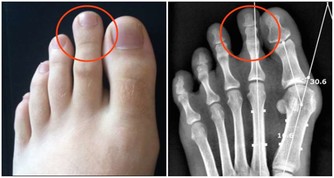

據美國紐約一家專門從事癌癥研究的權威機構透露,中國和日本婦女乳腺癌的發病率比西方低得多,這是為什麼呢?

科學家在比較了世界各國的三餐食譜後得出結論:是由於中國和日本婦女多吃大白菜的緣故。

調查資料表明,每10萬名婦女中,每年乳腺癌的發病率為:中國9人,日本21人,北歐84人,美國91人。